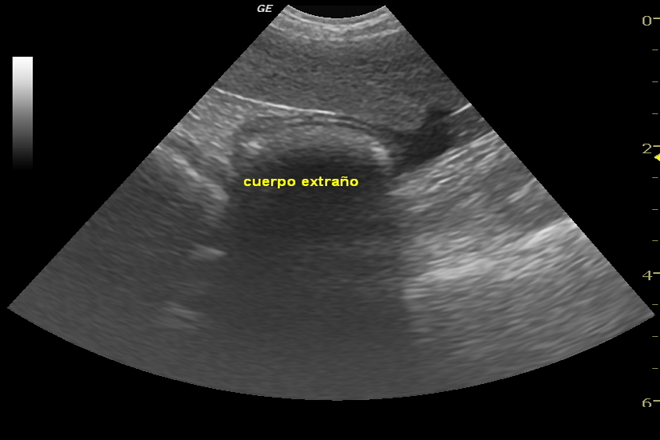

En la actualidad, no existe sólo una forma de detección de materiales pues se depende del tipo de material en estudio pudiendo por lo tanto encontrar tecnologías como los rayos X con diferentes niveles de sensibilidad, los escaners de rayos gama, la espectrometría de movilidad iónica, la de pulso de inducción de alta sensibilidad, etc., que son en general costosas por lo que en las necesidades vigentes se encuentran la aplicación de tecnología y métodos en diversas áreas de los procesos de producción que sean relativamente baratos. A éste decir se acopla el uso de las ondas ultrasónicas que pueden medir confiable y rápidamente el espesor del material y su integridad detectando defectos internos como huecos, fracturas o fisuras, y otras propiedades físicas de los mismos sin afectar sus características mediante el uso del adecuado transductor, de la frecuencia de operación, la potencia de excitación y el tipo de convergencia del haz ultrasónico.